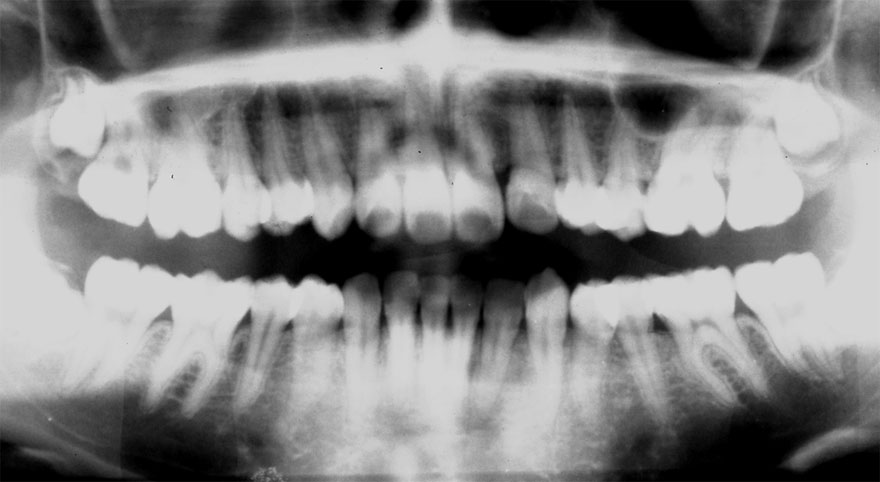

開始年齢 10代

初診時 16歳 女性

若年性歯周疾患

27年後 43歳